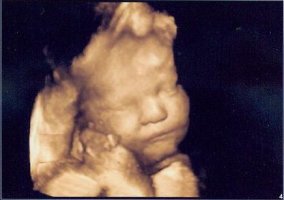

Tolle Fotos hier übrigens. Stelle mal ein paar neue von unserer Kleinen rein. Am Freitag hat sie sich das erste Mal bequemt, ihr Gesicht zu zeigen. Ich war echt fasziniert. Es ist so schön, dass Baby zu sehen. Bin jetzt schon total verliebt. Was soll das erst werden, wenn sie da ist?! 😛feif

• 8.jpg

8.jpg

82,3 KB · Aufrufe: 426

• 9.jpg

9.jpg

78,3 KB · Aufrufe: 424

• 10.jpg

10.jpg

85,3 KB · Aufrufe: 428